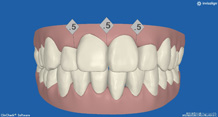

2か月後です。反対咬合は治っています。現在は正常な噛み合せになりました。

これからまだ永久歯に生え替わるので、注意深く定期的に観察していきます。生え替わった後に、また反対咬合になりこともあります。